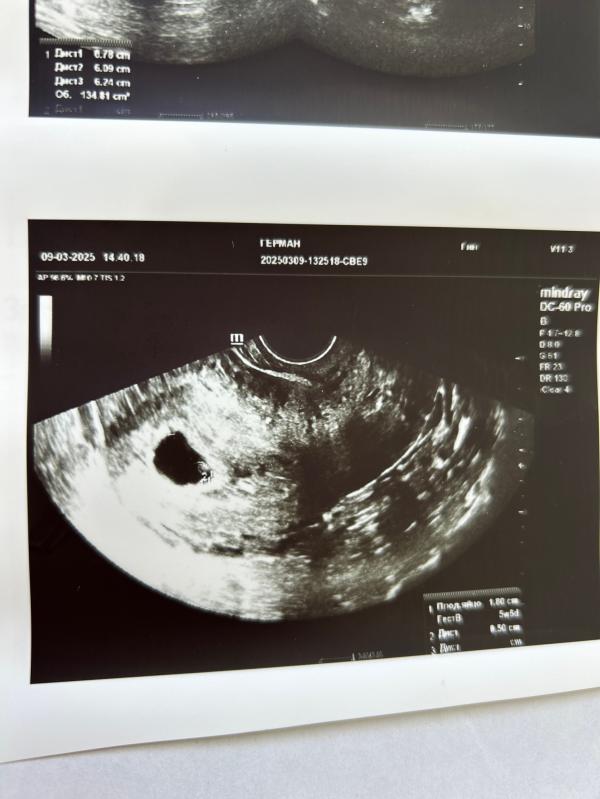

Сходила на УЗИ поставили Анэмбрионию, отправили на чистку . На первом УЗИ плодное яйцо было 9,8 ( поставили 5,5 недель) . Сейчас плодное яйцо 18 мм, и опять поставили срок 5,5 недель .

Я уже 4 раз переделываю 🤷♀️, плодный пузырь сегодня уже 22 мм..

Там нет эмбриона, в плане не видно, выросло плодное яйцо. Но может и срок маленький, конечно. В общем, только ждать и переделывать узи(